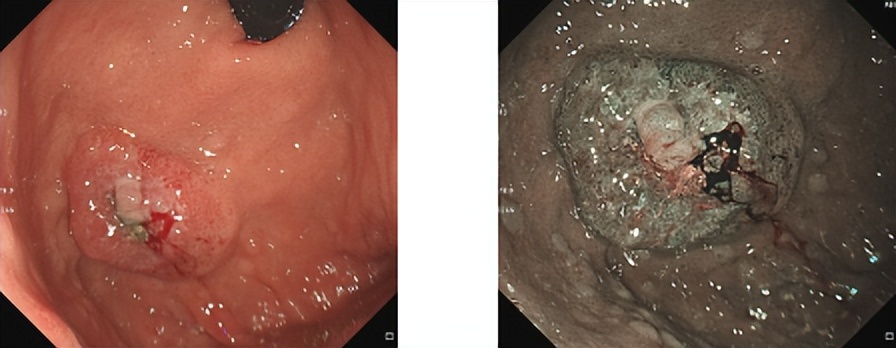

胃镜

胃底近后壁见3*3.5cm大小隆起,宽基底,表面凹凸不平,见糜烂溃疡,质脆,表面结节状充血水肿,有自发性及接触性出血。肠镜检查未见器质性病变。